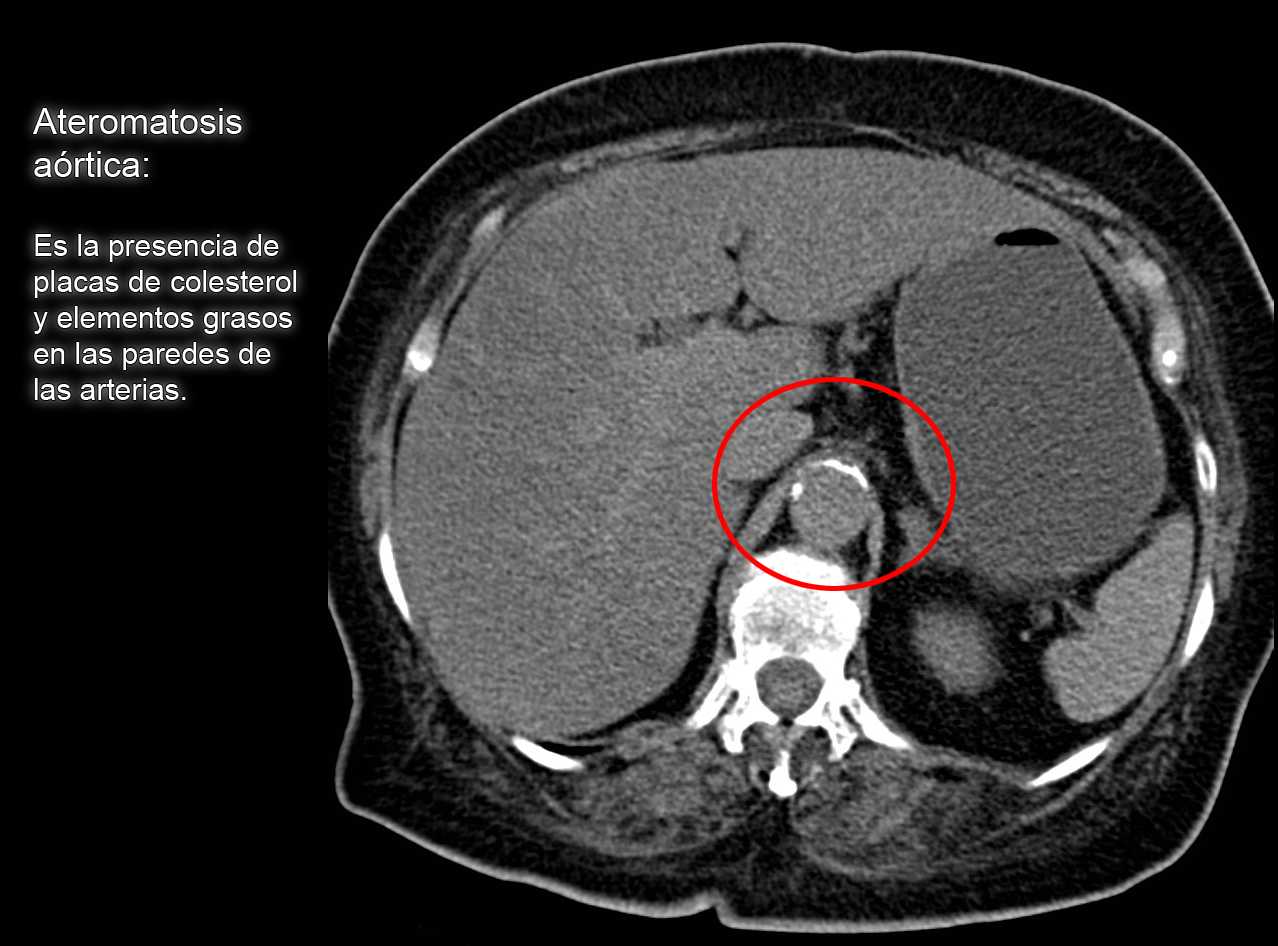

O que éateromatosedasartériascarótidasinternasintracraniana?Ateromatoseaórtica: o que é, causas, sintomas e tratamento - Vitat.Normal coronaryarteryand different types of Atheromatous plaque with